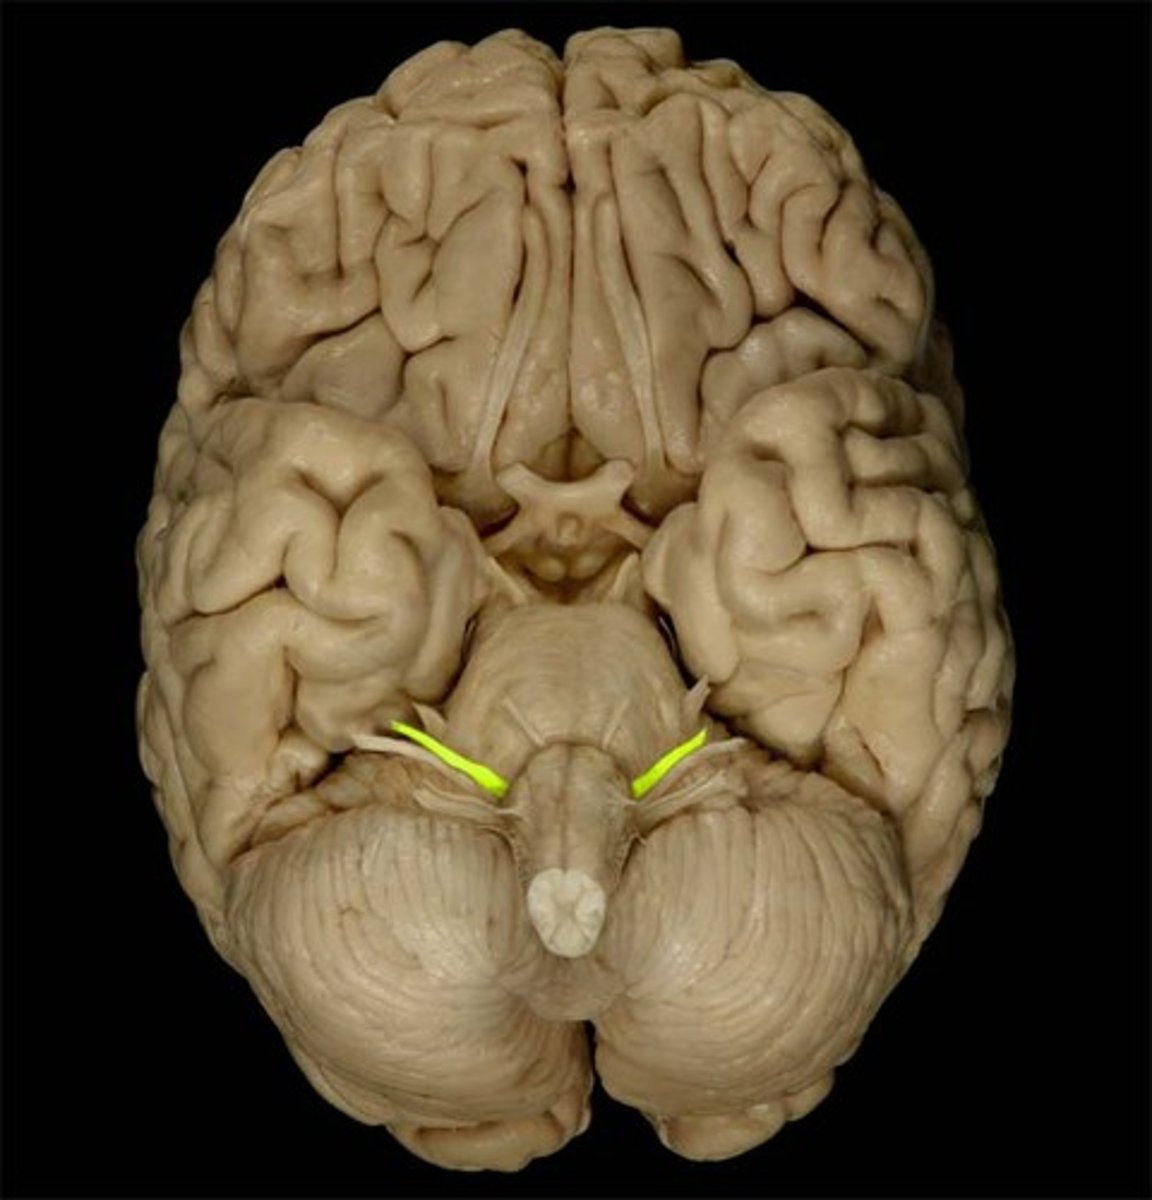

IV Trochlear

motor eye movement